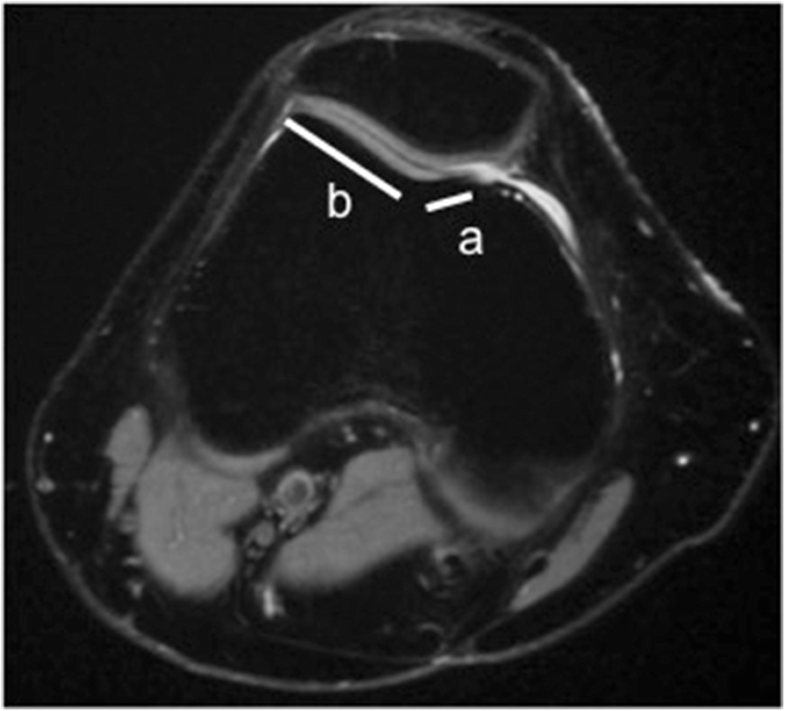

Patellar maltracking in a symptomatic left patient knee. Compared to What Does Patellar Maltracking Mean Patellar tracking disorder is a type of knee pain caused by the patella moving out of the groove. Learn about the common factors, signs, and conservative options for this condition from idaho. Patella tracking disorder is when the patella does not move within the groove. Patellar maltracking is a disorder of the patellofemoral joint caused by imbalance of the dynamic. What Does Patellar Maltracking Mean.